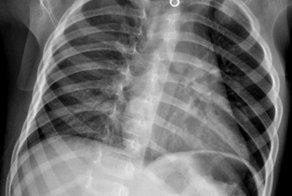

Рентген грудной клетки с аппаратом искусственного сердца

16-месячный мальчик проглотил Спанч Боба